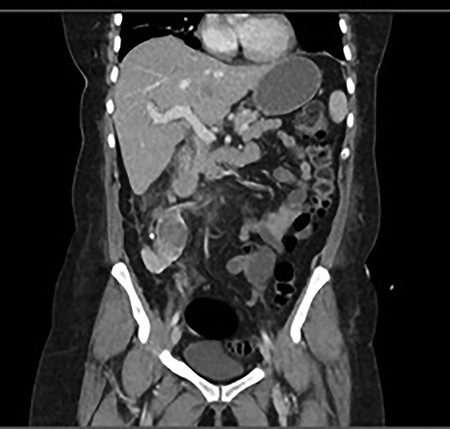

A 60-year-old lady presented to the emergency department with a 1-day history of migratory right lower quadrant pain, diarrhea and associated fevers and rigors. She had a background history of previous diverticulitis and hypertension. On examination, she was shocked with a blood pressure of 86/52, was borderline tachycardiac at 95 bpm, she was tender in the right lower quadrant with guarding and laboratory tests showed acute kidney injury (AKI) with an eGFR of 37 ml/min (previously normal renal function) and a white cell count of 32.9 (109/L). She was referred to the surgical team with a clinical diagnosis of acute appendicitis with an Alvarado score of nine [3]. On further investigation, her urine microscopy showed >500 leucocytes. Because of her age, highly positive urine microscopy (MCS) and AKI, a non-contrast computer tomography (CT) was performed, which showed a malrotated right ectopic kidney with perinephric stranding and a non-obstructing 6 mm calculus in renal pelvis (Fig. 1).

Coronal and transverse CT showing a malrotated right kidney with a non-obstructive calculus and marked perinephric stranding. This ectopic kidney also has an abnormal axis, facing anterolaterally.